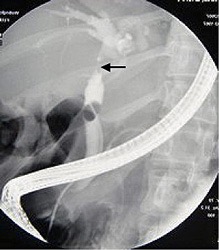

Picture taken at ERCP showing a cancerous obstruction high up in the common bile duct